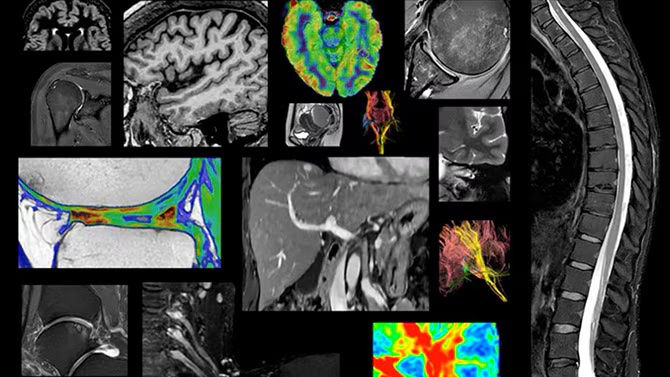

Intelligent technology

The industry’s first integrated simultaneous time-of-flight PET detector** with premium 3T MRI